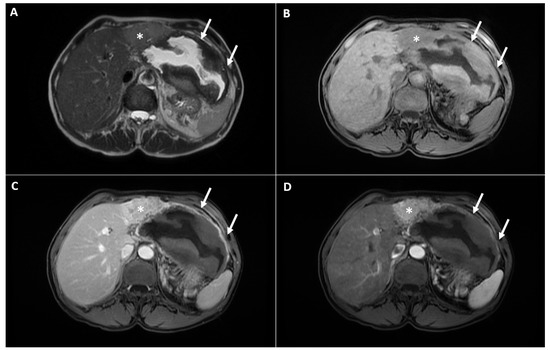

2. Case Report